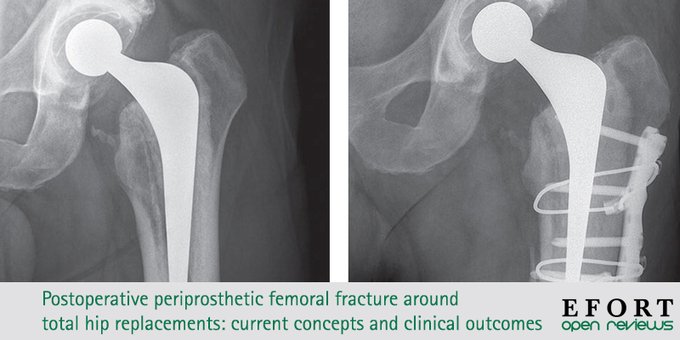

📄 Rising incidence of postoperative #periprosthetic femoral #fracture presents a significant clinical & economic burden.

A detailed understanding of risk factors is required to guide preventative strategies https://t.co/lcBR61t9qM#OpenReviews #surgery #implants #prostheses #THR pic.twitter.com/9HPYkhmWZZ

Fractura periprotésica posoperatoria de fémur alrededor de las artroplastias totales de cadera: conceptos actuales y resultados clínicos

La creciente incidencia de fracturas periprotésicas de fémur postoperatorias (PFF) presenta una carga clínica y económica significativa.

Se requiere una comprensión detallada de los factores de riesgo para orientar las estrategias preventivas.

Los diferentes vástagos femorales tienen características únicas y las estrategias de manejo deben adaptarse de manera adecuada.

Se carece de consenso con respecto al tratamiento de los PFF alrededor de vástagos bien fijados, pero la cirugía de revisión puede proporcionar resultados más predecibles para los patrones de fractura inestables y las fracturas alrededor de los vástagos de deslizamiento cónico pulidos.